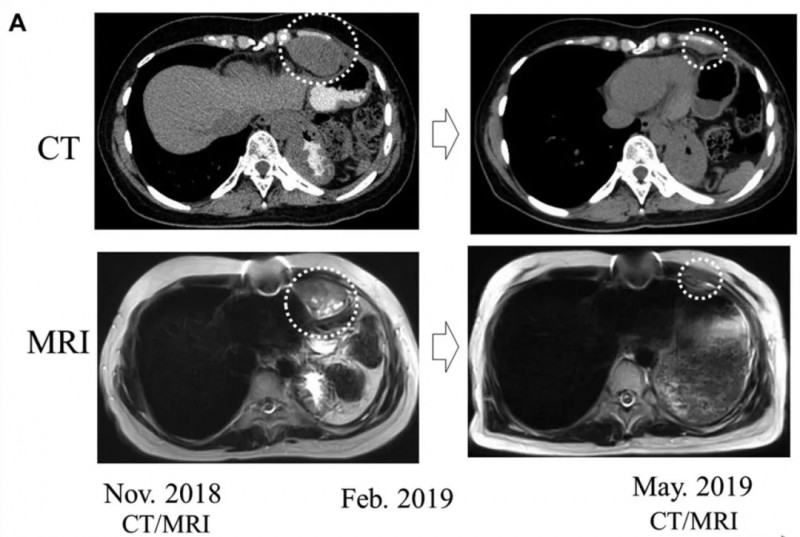

病例3(53岁女性恶性胸腺瘤胸膜转移患者)

2004年术后胸壁、胸膜反复复发,2018年10月左胸壁出现6cm复发肿瘤;2018年12月起接受新抗原肽DC疫苗治疗。

结果显示:2019年5月复查CT证实,同一位置的肿瘤明显缩小(详见下图)。

▲图源“Anticancer research”,版权归原作者所有,如无意中侵犯了知识产权,请联系我们删除